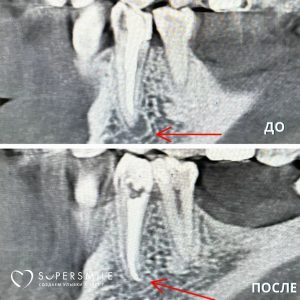

Диагностика

Для постановки точного диагноза и дифференциальной диагностики, доктор направляет вас на рентгенологическое обследование, в некоторых случаях необходима КТ-диагностика. Затем оценивает результат и назначает дальнейшее лечение.

Обтурация (пломбирование) корневых каналов

Корневые каналы тщательно высушивают специальными бумажными пинами (турундами) и обтурируют (пломбируют). Чаще всего для обтурации используют гуттаперчевые штифты и силер (специальная паста для пломбирования корневых каналов). Но также в нашей клинике вы найдете применение разогретой или термопластифицированной гуттаперчи. После пломбирования корневых каналов обязательна рентгенологическая диагностика качества обтурации корневых каналов.

Работы наших специалистов по лечению каналов зуба